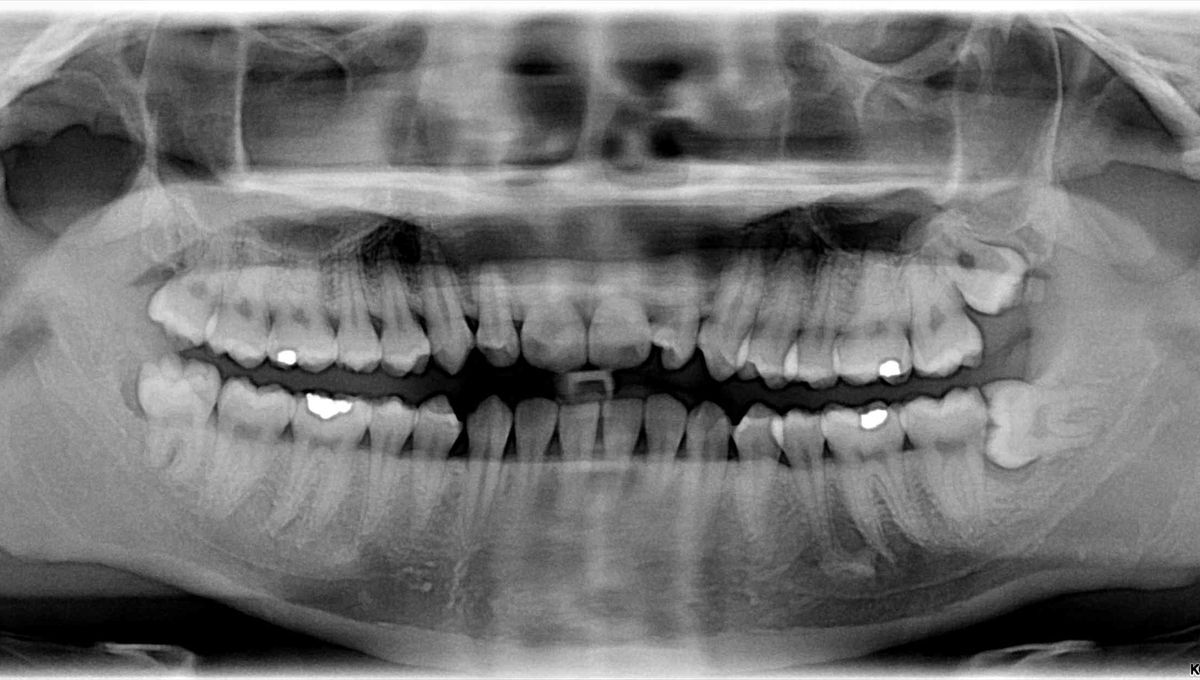

Why Do People Have Wisdom Teeth?

Two dental experts explain.